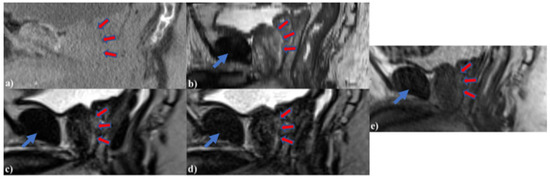

Both 3D HASTE and 3D TSE were qualitatively optimized for urethra visualization on low-field MRgRT using four healthy male volunteers. Echo time (TE), relaxation time (TR), and voxel size were tuned to provide urethra contrast while maintaining sufficient SNR. Additionally, the number of averages was tuned to increase image SNR and minimize motion/ghosting artifacts, while maintaining acceptable scan times. Figure 1 and Figure 2 show the MRgRT 3D HASTE and MRgRT 3D TSE optimization. Optimization steps for MRgRT 3D HASTE and TSE were similar. Volunteer 1 HASTE 1 and Volunteer 2 TSE 1 (baseline) show a noisy urethra with some urethral contrast. By increasing the number of averages to 6 and 4, the scan SNR improved and the final scan time was increased to 8:06 min and 7:14 min, respectively. Increasing TE to 407 ms (Volunteer 2 HASTE 1) resulted in lower SNR, but greater urethral contrast as T2-weighting increased. Conversely, decreasing TE to 135/133 ms (Volunteer 2 HASTE 2/Volunteer 2 TSE 2), resulted in higher SNR, but less urethral contrast as T2-weighting decreased. Increasing TR to 3000 ms (Volunteer 4 TSE 2) slightly improved SNR, but lowered urethral contrast, as prostate and urethral signal intensity were able to fully recover. Ultimately, TE of 246/250 ms and TR of 1800/2000 ms for MRgRT 3D HASTE/TSE was selected to provide adequate SNR and urethral contrast. Lower resolution (Volunteer 2 HASTE 2 and 3) of 2.0 mm isotropic, compared to 1.5 mm isotropic, provided higher SNR; however, 1.5 mm isotropic was selected to capture the prostatic urethra’s fine structure. Lastly, sagittal acquisition was preferred over axial acquisition for easier urethra visualization and delineation.

Figure 1. MRgRT 3D HASTE optimization scheme using healthy male volunteers (red arrows pointing towards prostatic urethra).